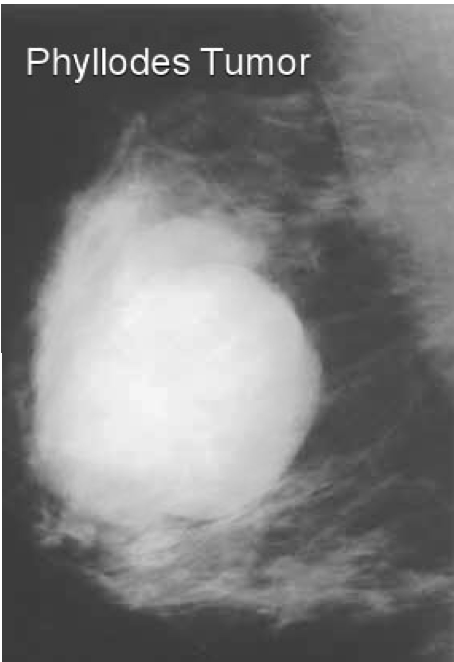

Phyllodes tumor

Can be malignant

How do you treat a Phyllodes Tumor

Excision required